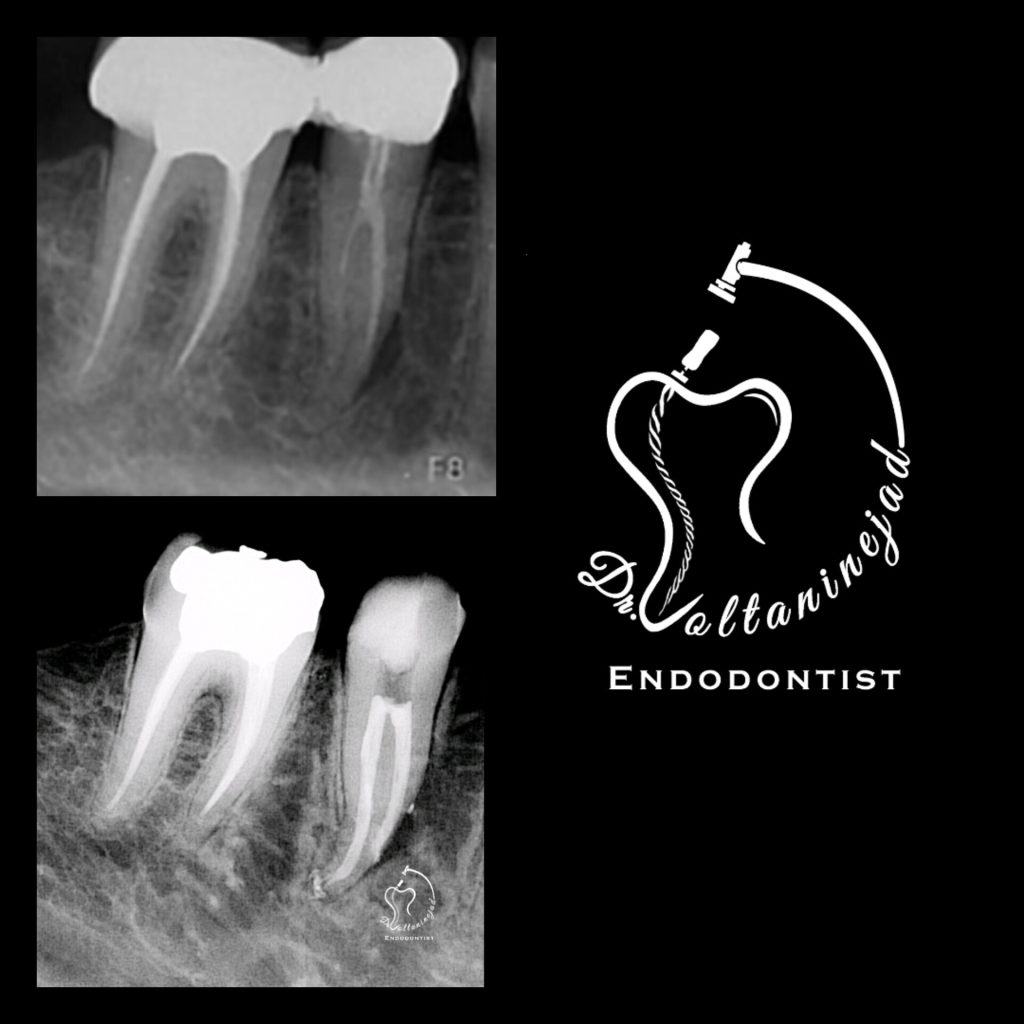

🔹 خارج کردن فایل شکسته از کانال

• شرح کوتاه: بیمار با درمان ریشه نامناسب و فایل شکسته در کانال مراجعه کرد. فایل با میکروسکوپ خارج شد و درمان ریشه مجدد انجام شد.

• نتیجه: رفع درد و حفظ دندان بدون نیاز به جراحی.

خارج کردن فایل شکسته